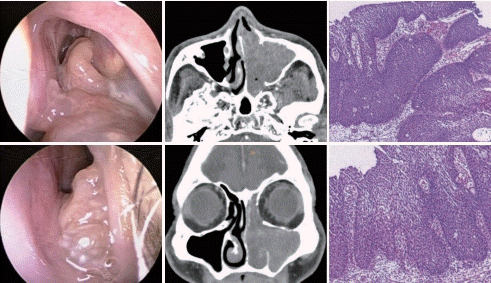

60대 남자 환자가 수개월 전부터 심해진 좌측 코막힘을 주소로 내원하였다. 다음은 수술 전 좌측 비내시경, 전산화단층촬영, 조직검사 소견이다. 이 질환에 대한 설명으로 맞는 것은?

해 설 반전성 유두종은 비부비동의 양성 종양으로 골파괴 소견은 흔하지 않으며 직접적인 골침습보다는 압박괴사를 유발한다. 반전성 유두종은 비부비동에서 발생하는 종양 중 0.5~4%를 차지하는 비교적 드문 종양이며, 주로 일측성으로 발생하지만 양측성도 약 4.9%로 보고된다. 과거 광범위 근치술이 보다 선호되었으나 최근에는 비내시경하 절제술이 수술의 표준으로 자리매김하게 되었다.